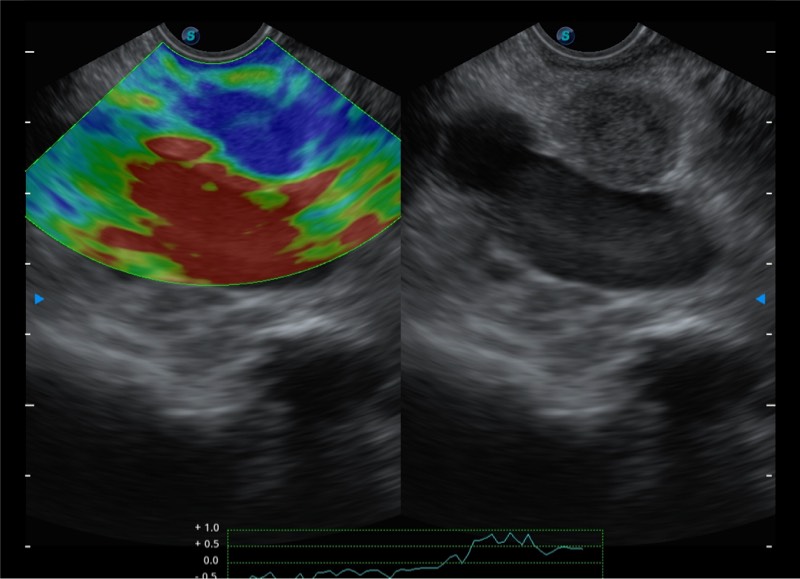

基于二十年的超声技术积累,竞技宝(JJB)官方网站提供了最新一代的独立超声主机,在提供高质量图像的同时满足多学科使用。具备常见多普勒技术并提供弹性成像、声学造影等高端影像技术。新一代传感器具有更强的抗干扰能力并减少图像伪影。

150°超声扫描角度

4-12MHZ宽频输出